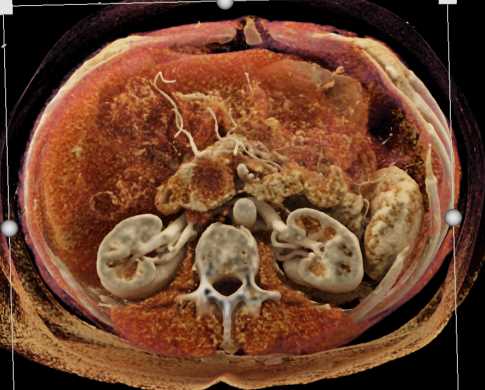

Neuroendocrine Tumor Body of Pancreas